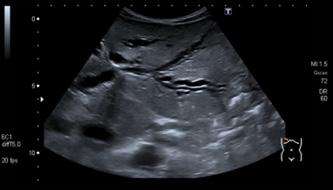

Ecocardiograma

Confirma el derrame pericárdico (efusión > 50 ml).

Espacio anecoico entre el pericardio y el epicardio evalúa el volumen.

<10 mm: pequeño (300 ml)

10-20 mm: moderado (500 ml) > 20 mm: severo (> 700 ml)